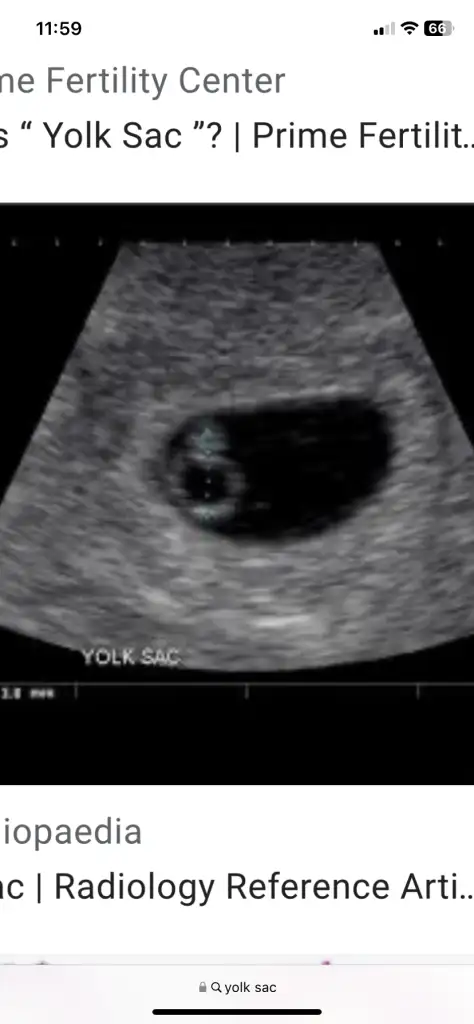

Ben de perşembe günü gideceğim. İnşallah görürüm bebeği ve kalp atışını. Benim ultrason görüntüsü böyleydi

Eklentiler

• 822099A0-AA97-47BA-B90F-4E0698483A05.webp

822099A0-AA97-47BA-B90F-4E0698483A05.webp

109,5 KB · Görüntüleme: 433

• E962DBEE-06A8-468D-A4EA-C7CE42A48A64.webp

E962DBEE-06A8-468D-A4EA-C7CE42A48A64.webp

52,6 KB · Görüntüleme: 437